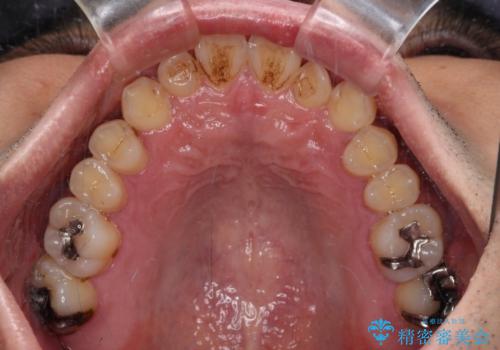

内側に引っ込んだ歯を治したい インビザラインの矯正治療

- 前歯のデコボコとクロスバイトを治したいとのことで来院された患者様です。

上下顎ともに歯列全体の側方拡大とIPR(歯と歯の間を削る)によってデコボコとクロスバイトが解消するように設計し、インビザラインにより治療を行うこととしました。

反対咬合特有の治療途中の前歯の干渉が長く続き、治療中に食事をとりにくく、ご迷惑をおかけしました。

前歯の咬み合わせの調整などを行い、安定した咬み合わせに仕上げることができました。